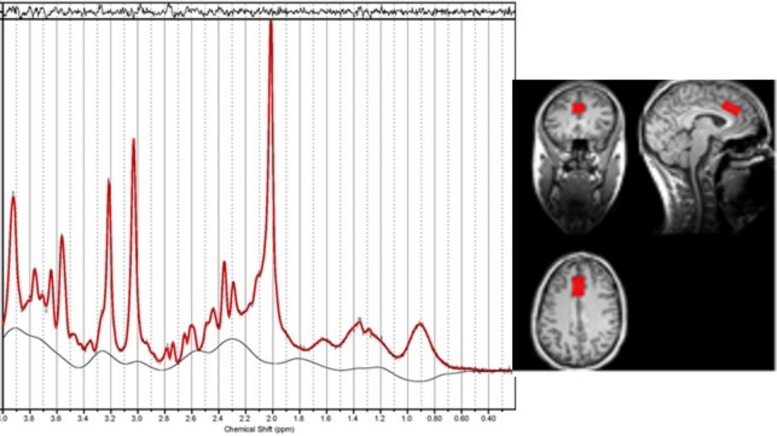

Voxel Placement

The MR spectroscopy voxel was positioned in the dACC using the T1-weighted image. The voxel was positioned in the following way: locate the mid-slice of the corpus callosum on the sagittal slice, then place the voxel directly above the superior and posterior genu of the corpus callosum with the long axis aligned with them (see Figure 1). The voxel size was 15 × 20 × 25 mm3.